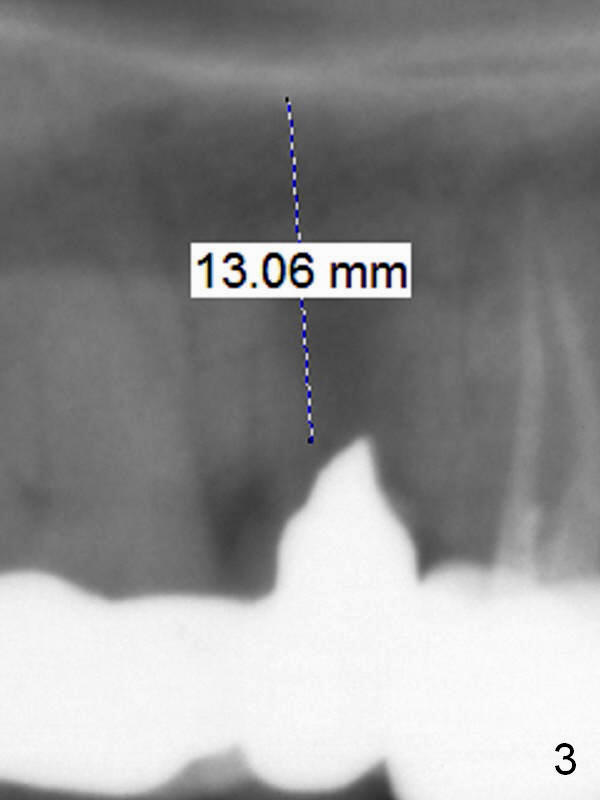

A 42-year-old man returns with chief complaint of chipped tooth at #3. Crowns at #3 and 4 are splinted (Fig.1). The tooth #4 is discolored (^). X-ray exam shows post (P) -induced Root (R) split with severe bone loss at #4 (Fig.2). To decrease periimplantitis, use an implant as narrow as possible (4 mm) and as long as apical bone allows (13 mm, IBS, Fig.3). Section the retainer at #3 and remove the tooth #4 (Metronidazole). Prepare PVS impression to record socket morphology. Magic Expanders are to be applied for osteotomy and sinus lift if possible. Finally fabricate splinted provisional at #3 and 4.